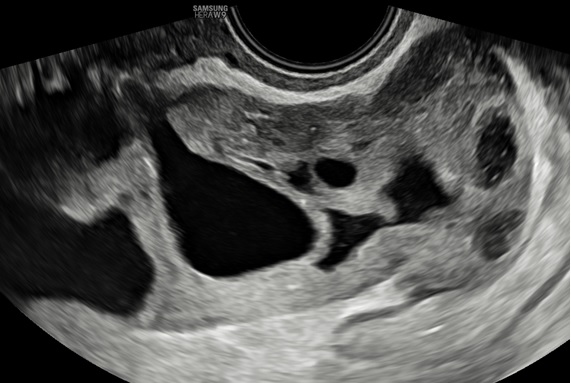

– Siêu âm: Tử cung và 2 buồng trứng bình thường. Ở cùng đồ sau có cấu trúc echo kém không đồng nhất dạng hình ống, có vách ngăn dày thông nhau, kích thước # 84x 89x 37 mm, bờ trong thành u không trơn láng, bên trong có nhiều mảng echo kém dạng mô đặc, tăng sinh mạch máu mức độ 2. Bụng và cùng đồ: không dịch.

– Chẩn đoán siêu âm: Huyết tụ thành nang. Chẩn đoán khác: áp xe phần phụ.

Hình 4: Siêu âm ngã âm đạo thang xám cho thấy khối u hình ống ở cùng đồ sau nhiều vách ngăn dày thông nhau.

Hình 5: Siêu âm ngã âm đạo cho thấy thành u có tăng sinh mạch máu độ 2